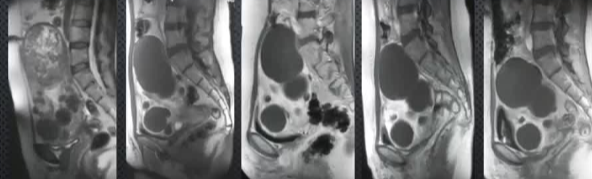

无症状复发![]() 分别是基线→3月→1年→2年→3年 【Pelage JP 2004】 子宫肌瘤有治疗有需求,子宫动脉栓塞术(UAE)具有应用价值。本研究通过3年MR随访,旨在评估UAE治疗子宫肌瘤后的长期磁共振(MR)成像结局,探讨UAE治疗后肌瘤梗死程度与长期预后的关联,为临床疗效评估提供影像学依据。 方法概述采用增强MR成像,动态监测肌瘤体积、灌注及症状变化,通过组间比较(t检验、卡方检验)分析梗死程度对结局的影响。研究对象为20例患者,在UAE术前、术后3个月及每年随访(最长3年)进行对比增强盆腔MR成像,分析肌瘤梗死程度、体积变化、症状改善及新发肌瘤情况。其中17例患者在基线、治疗后3个月和3年进行了对比增强MR成像。 核心结果